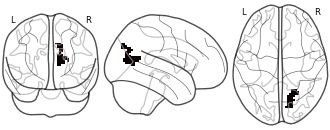

"name": "Multi_VBMsmaller_fMRIdecreased",

"description": "Multi-modal analysis in BPD. Brain regions exhibiting smaller gray matter and decreased activation during emotion processing in BPD compared to healthy controls. Note: Results were thresholded at p<.0025. Note2: Results were updated (see Erratum for this publication).",